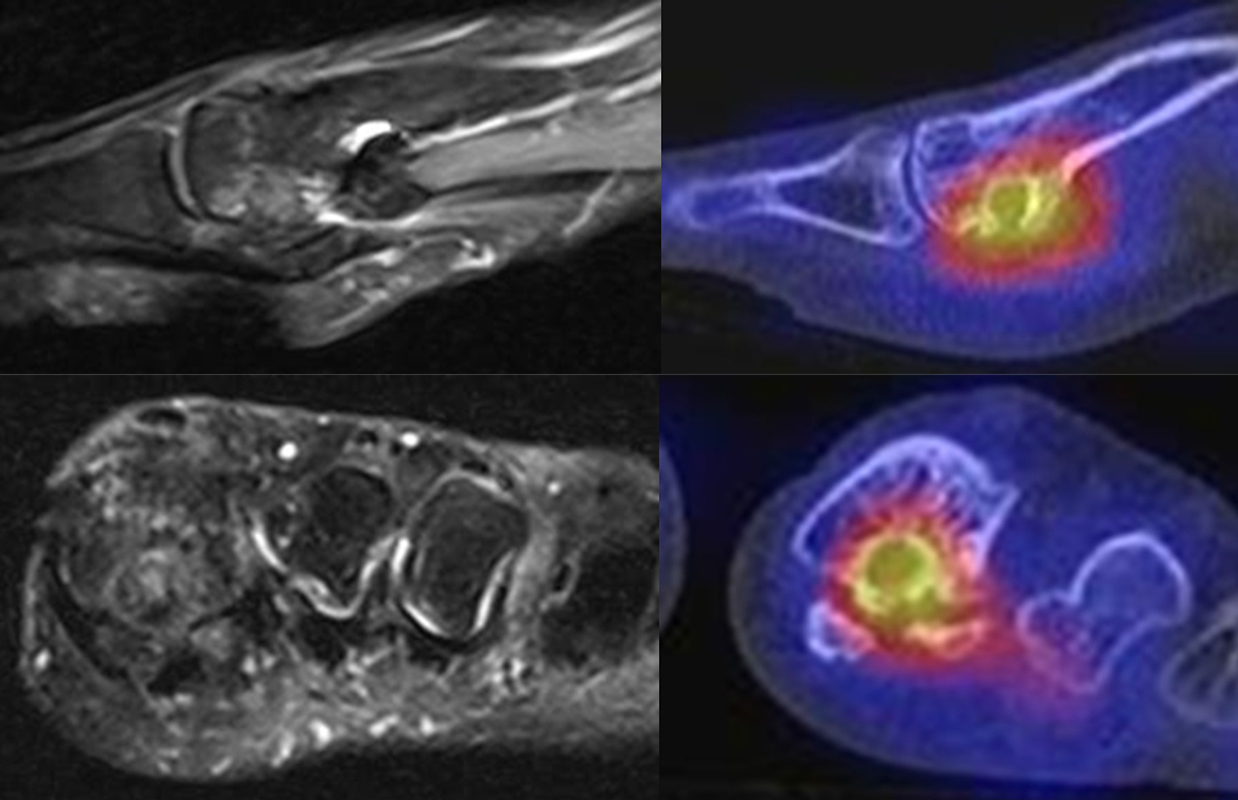

Abbildung 8.5.a bis f: Patientin mit anhaltenden Schmerzen bei Z. n. Hallux valgus-OP vor 8 Jahren. Im MRT 7 Wochen vor der SPECT/CT kein wegweisender Befund bei auch deutlichen Artefakten durch Metallabrieb. Im SPECT/CT Nachweis von arthrotischen Veränderungen im Metatarso-Sesamoid-Gelenk mit einem intraossärem Ganglion im Köpfchen von

Os metatarsale I.

Abbildung 8.6. a bis f: Patientin mit Z. n. Talusfraktur vor 2 Jahren, welche mit zwei Schrauben osteosynthetisch versorgt wurde. Seither progrediente Schmerzen im linken Fuß. Ein MRT 8 Monate vor der SPECT/CT-Untersuchung war nicht eindeutig bzw. nicht wegweisend. Im SPECT/CT aktivierte posttraumatische osteochondrale Läsion talusseitig im linken unteren Sprunggelenk mit einem abgrenzbaren Ossikel bis 5 mm Größe und angrenzenden arthrotischen Veränderungen. Reizlose Schrauben im linken Talus.

Abbildung 8.8.a bis d: Patientin mit bekanntem Knick-Senk-Fuß. Anamnestisch Schmerzen in beiden Füßen, links > rechts seit ca. 2 Jahren. Fragestellung: Status der bekannten Fußwurzelarthrosen vor geplanter OP. Neben, unter anderem fortgeschrittenen Arthrosen im Naviculo-Cuneiforme-Gelenk, Nachweis einer Tibialis posterior-Sehnen-Tendinitis mit begleitender Periostitis/Ostitis am Malleolus postero-medial. Abbildung 8.8.a und b: in der Frühphase (2 Minuten nach Tracerinjektion) sind lineare Anreicherung des Tracers im Verlauf der linken Tibialis posterior Sehne zu sehen.  In der  Mineralisationsphase im SPECT/CT begleitende Periostitis/Ostitis am Malleolus postero-medial. Abbildung 8.8.c und d: Der Blick auf das CT im Weichteilfenster offenbart diffuse entzündliche Verdickungen im Verlauf der linken Tibialis posterior Sehne. Rechts unauffälliger Befund. Unten beispielhaft die schmerzhafte NC-Arthrose.

Abbildung 8.9. a bis c: Extern MRT-morphologisch V. a. Coalitio calcaneo-naviculare. Anamnestisch Schmerzen im linken OSG seit ca. 1,5 Jahren, gehäuftes „Umknicken“ des linken Fußes, Pes planus bds.. Abbildung 8.9.a zeigt die 3D-Früh-SPECT aus verschiedenen Blickwinkeln. Wie in Abbildung 8.8.a findet sich hier eine deutliche lineare Tracerakkumulation im Verlauf der linken Tibialis posterior Sehne. Abbildung 8.9.b: In der Mineralisationsphase wie auch im vorhergehenden Fall ossäre Reaktion postero-medial am Mallelolus medialis als Zeichen einer chronischen Tendinitis. Die Durchsicht der 7 Wochen zuvor angefertigten externen MRT bestätigte den Befund (er war leider nicht beschrieben worden). Im SPECT/CT wurde eine Coalitio ausgeschlossen.

Abbildung 8.10.a bis e: Patient mit Verdacht auf symptomatisches Os peronaeum. In der Früh-SPECT/CT eindeutiger Nachweis einer ausgeprägten Tendinitis der Peronealsehnen links. In der Mineralisationsphase Stessreaktion im Bereich eines mehrgeteilten Os peroneaum links und lateral Calcaneus.